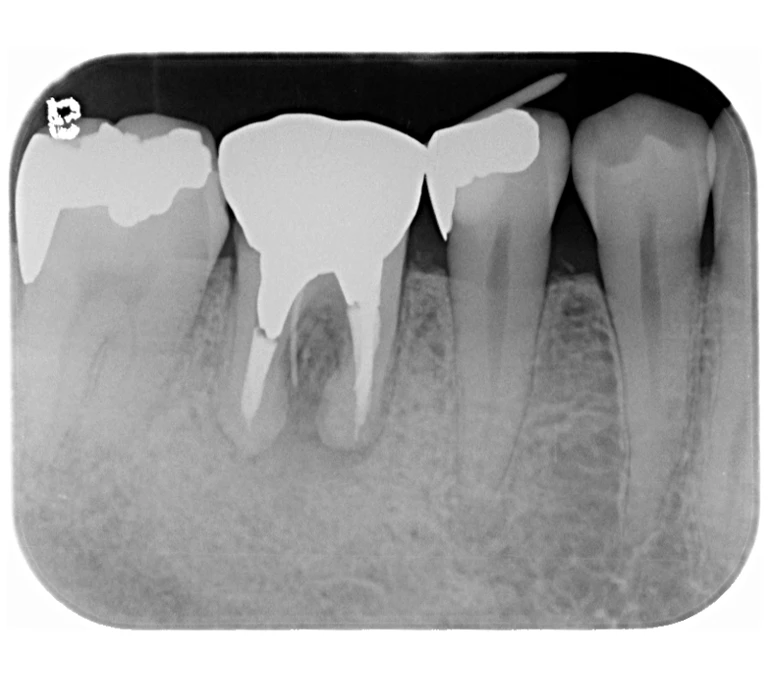

case 2.

治療前

治療後

| 主訴 | 左下歯ぐきの腫れ。 |

|---|---|

| 治療期間 | 約2か月 |

| 治療費 | 約1万5千円 |

| 治療内容 | ラバーダム、マイクロスコープ下にて根管治療を施術。 歯ぐきの腫れ、痛みや違和感が消失したため根管充填、支台築造(土台の製作)を行った。治療後の写真は矯正治療を行うことになったため仮歯を装着した状態。 |

| 治療のリスク | マイクロスコープやCTを使用し、可能な限り精密な根管治療を行っていますが、歯根の形態や病変の大きさ、過去の治療履歴などにより、治癒が得られない場合があります。また、治療後に再感染や歯根破折が生じることもあり、その場合は再治療や抜歯が必要となることがあります。 治療結果には個人差があり、すべての症例で同様の経過を保証するものではありません。 |